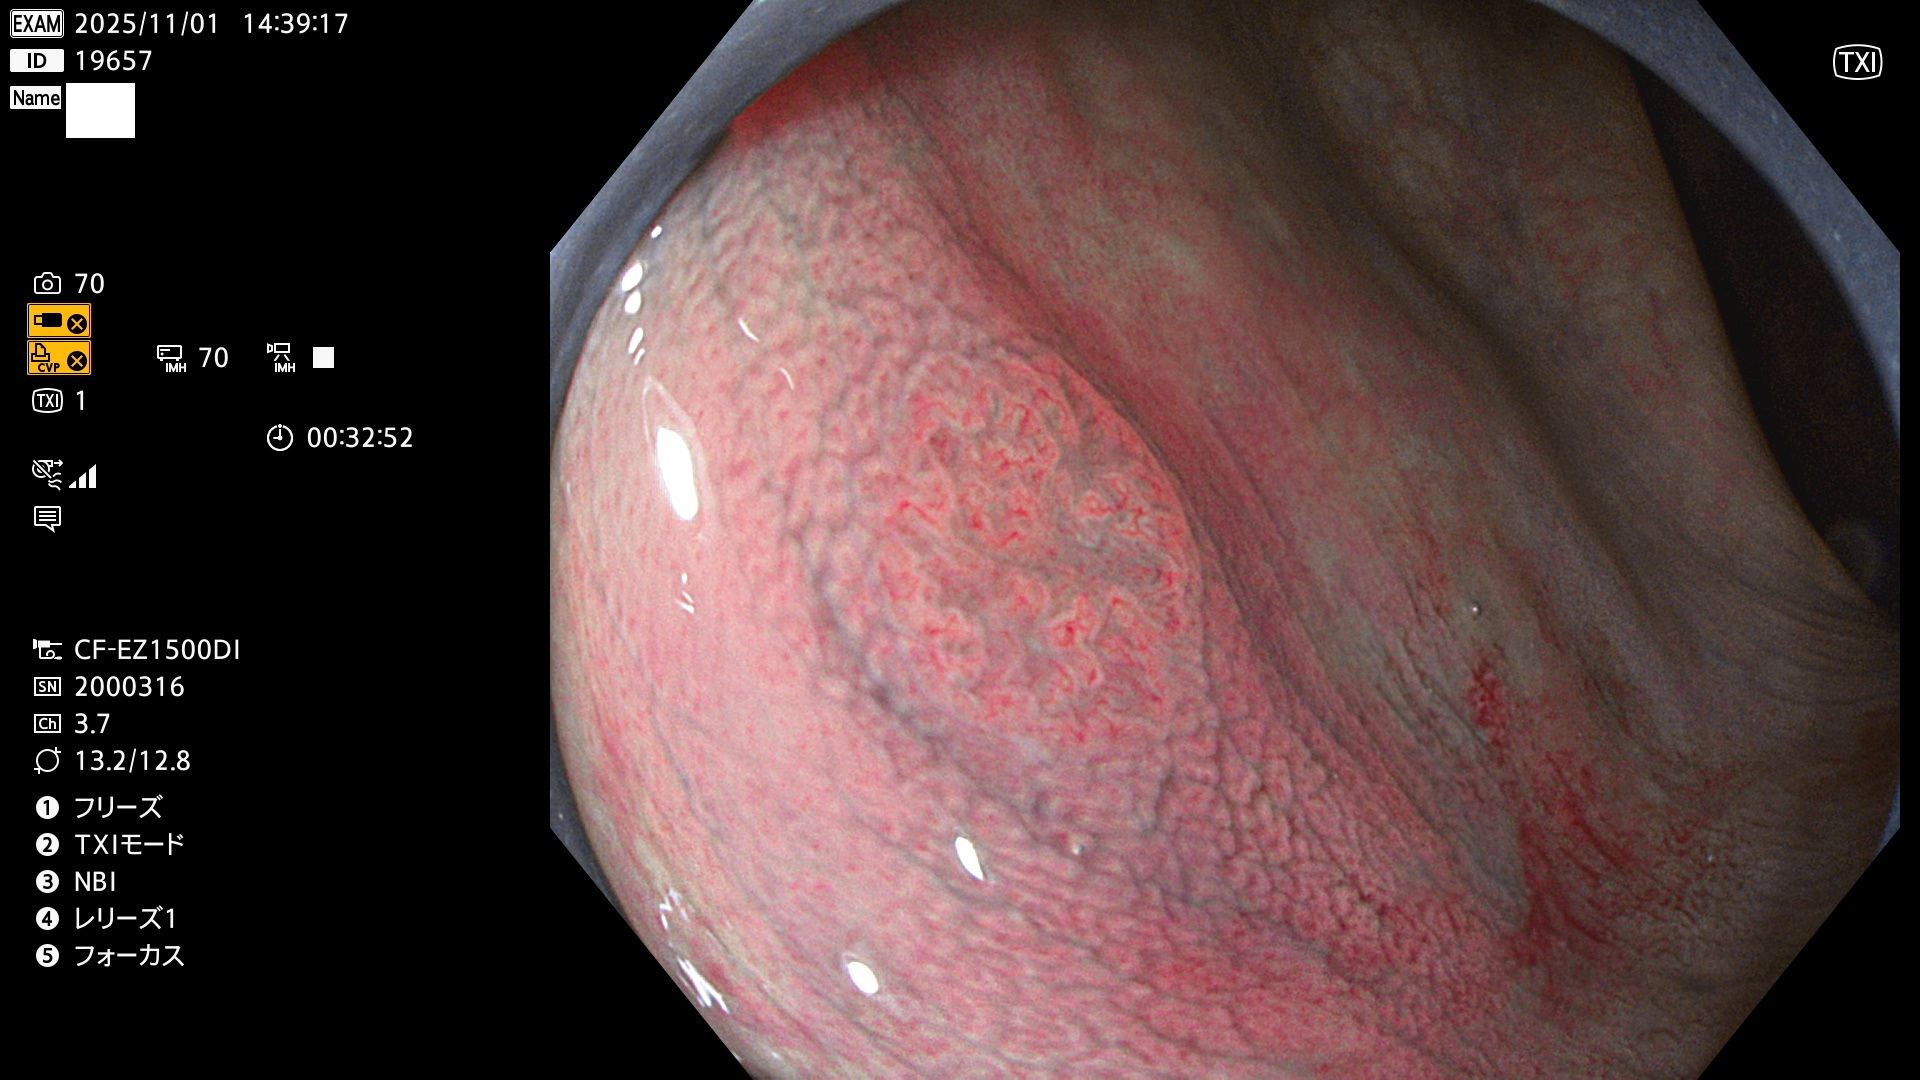

完全に平坦な物をUb、陥凹している物をUcと呼びます。Ubは認識が困難で、Ucはびらん(炎症)と紛らわしいために見落とされやすく、「内視鏡後・大腸癌」の原因になります。

専門的)Uc=De Novo癌? 内視鏡の解像度が低かった時代、このような説もありました。しかし今日の高精度内視鏡では良性の微小なUc型腺腫(APC遺伝子異常の腺腫)が日常的に見つかります。Ucこそが多段階発癌(Adenoma-Carcinoma Sequence)のMain Routeです。

毎週の検査(木・金・土・日)に発見されたUbとUc型・腺腫を、その週の日曜の夜にUPし1週間、提示します。

2025年10月30日〜11月2日の4日間(40件)9個 (Uc_ADR=9個/40人=23%)